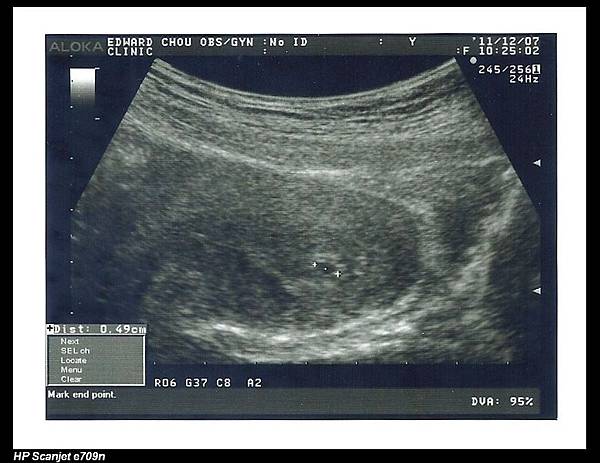

寶寶才 0.49cm,下次產檢是二週後,也就是第七週,到時若有心跳,一切就更穩定了。